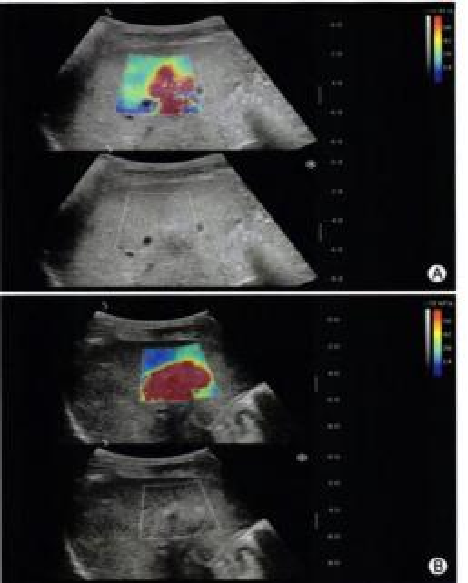

超声造影

image.png

医生可以更准确地识别和评估肿瘤、炎症、血栓等病理变化,从而提高诊断的准确性和可靠性

可以实现实时监测,特别是在手术过程中,帮助医生即时评估治疗效果和发现潜在问题

可以提供关于血流动力学的重要信息,例如评估血管的通畅性、血流速度和分布情况,这对于诊断动脉硬化、栓塞等疾病非常有帮助